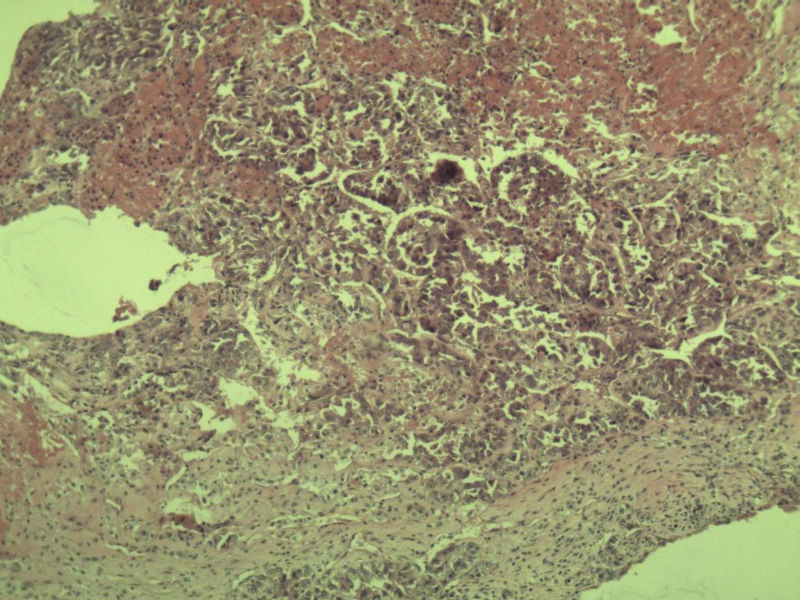

女 70岁 右颈部 头皮 多发皮下结节      取颈部部分结节送检 灰白小组织 1 块,直径 0.4 cm。 请问这个是什么?

肿瘤细胞大,上皮样,核空泡状,核仁明显,胞质嗜酸性或透明。

考虑:恶性黑色素瘤?

近心型上皮样肉瘤?

软组织透明细胞肉瘤?

上皮样多形性脂肪肉瘤?

等免疫组化标记!

此片染色欠佳,取材或切面也有问题,加大了诊断的难度,恶黑确实需要考虑,但其他一些转移癌也需要排除,比如肺癌之类的,还是期待免疫组化!